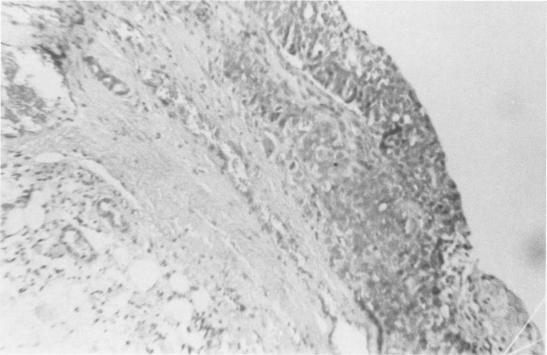

Carcinoma arising in the wall of a breast cyst during pregnancy.

A 23-year-old patient developed a carcinoma in the wall of a breast cyst during the second trimester of an otherwise uncomplicated pregnancy. A review of the literature revealed 7 reported cases of carcinoma of the breast arising in a cyst wall. However, none of these these cases has been associated with pregnancy. The relationship of fibrocystic disease and carcinoma of the breast is discussed. The possible influence of pregnancy and age on the prognosis of this patient are also considered.

一名23岁的患者在妊娠中期,于一个原本无并发症的乳腺囊肿壁上发生了癌变。文献回顾显示,有7例报道的乳腺癌发生于囊肿壁。然而,这些病例均与妊娠无关。文中讨论了纤维囊性疾病与乳腺癌的关系。还考虑了妊娠和年龄对该患者预后可能产生的影响。